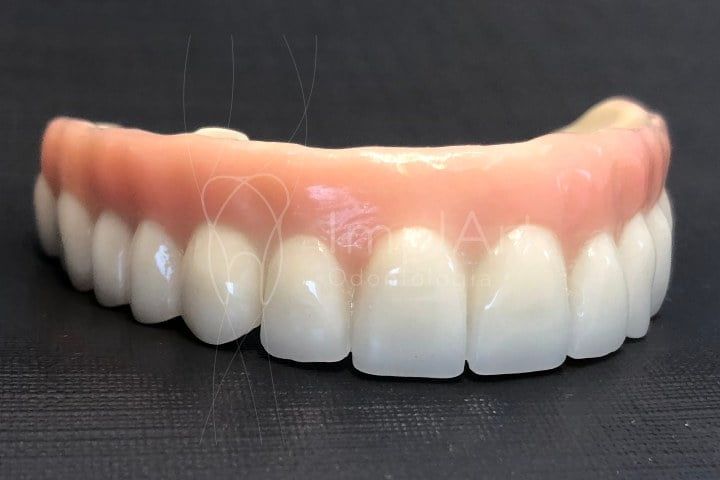

A prótese protocolo consiste em uma prótese total fixa, que é parafusada sobre implantes dentários. Esses implantes são inseridos cirurgicamente no osso maxilar ou mandibular, de modo a funcionar como raízes artificiais. Esse processo inclui procedimentos protéticos cuidadosos para garantir uma adaptação de próteses perfeita. A cirurgia de implante dentario pode ser realizada junto a enxerto ósseo, caso seja necessário, na grande maioria dos casos.

As próteses protocolo são essenciais para a reabilitação protética, pois restabelecem não apenas a função mastigatória, mas também a estética facial e o conforto. Além disso, esses protocolos de prótese são fundamentais para melhorar a pronúncia e a confiança ao sorrir. Os procedimentos protéticos minuciosos garantem que o paciente obtenha uma reabilitação bem-sucedida e duradoura.

| Estética | Rigidez e aparência natural da prótese. |

Pacientes geralmente esperam uma melhora instantânea na função e estética após a colocação de suas próteses. Importante compreender que o tratamento envolve etapa de cirurgia de implantes dentarios, uso de prótese provisória, e após cicatrização dos implantes, e elaboração da protese fixa sobre implantes. Atualmente a Prótese de Zircônia é a mais moderna! a realidade muitas vezes inclui um período de adaptação à nova estética do sorriso e à nova mastigação.